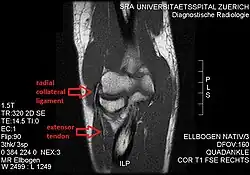

The radial collateral ligament (RCL), lateral collateral ligament (LCL), or external lateral ligament[Explain 1] is a ligament in the elbow on the side of the radius.

- the radial collateral ligament [proper] (RCL), from the lateral epicondyle to the annular ligament deep to the common extensor tendon[1]

- the lateral ulnar collateral ligament (LUCL), from the lateral epicondyle[3] to the supinator crest on the ulna. Near the attachment on the humerus this ligament is normally indistinguishable from the RCL and can be considered the posterior portion of it.[1] Martin 1958 described the distal part of the LUCL as "a definite bundle which normally crosses the annular band and gains attachment to the supinator crest, frequently to a special tubercle on that crest" but didn't name it.[4]